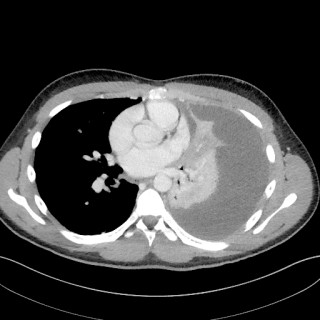

En yngre mann ble innlagt med venstresidige respirasjonsavhengige brystsmerter. Han hadde lett nedsatt allmenntilstand og feber. Det skulle bli et lengre sykehusopphold, der man diagnostiserte en uvanlig årsak til lungeaffeksjon. En tidligere frisk mann i slutten av tenårene ble via legevakt innlagt i sykehus etter ett døgn med venstresidige, respirasjonsavhengige smerter. Ved innkomst hadde han temperatur 37,6 °C, puls 117 slag/min, blodtrykk 104/57 mm Hg, respirasjonsfrekvens 24/min og perifer O2-metning på 94 % uten ekstra oksygentilførsel, og normale forhold ved klinisk undersøkelse...